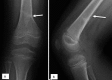

Figure 4.

13-year-old baseball pitcher. AP radiograph of the (A) right shoulder shows diffuse widening of the right proximal humeral physis (arrow). (B) For comparison, the left shoulder demonstrates normal width of the physis.